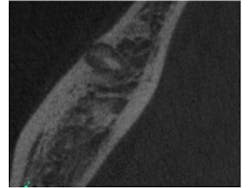

Fig. 2 is a sagittal slice through the lesion, further showing the mixed nature of the lesion. Figs. 3 and 4 are coronal and axial slices respectively. Both coronal and axial slices show that the PDL is intact around the root end and show that the lesion has caused erosion of the buccal cortical plate. Due to the unusual appearance of this lesion, an oral and maxillofacial radiologist also evaluated the CBCT scan.

Fig. 2: Sagittal slice through the lesion associated with tooth No. 30. Note the mixed appearance of the lesion. Note that the PDL can still be seen around the mesial root.